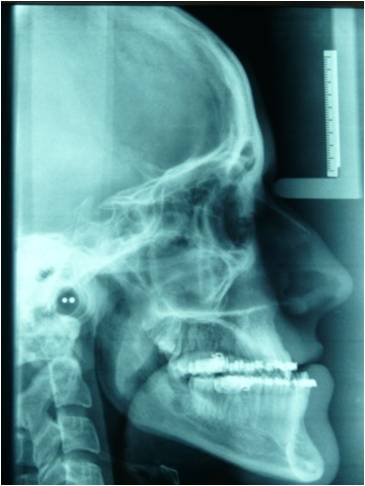

Correzione malformazioni cranio-facciali in età evolutiva ed adulta

Le alterazioni dello sviluppo dello scheletro facciale e delle ossa mascellari , di origina familiare o congenita , si caratterizzano anche con gravi modificazioni dell'occlusione con conseguenti problematiche funzionali ed estetiche. A questo proposito è molto importante intercettare la patologia di accrescimento osseo nell'età prepuberale ed eventualmente eseguire una terapia ortodontica dapprima intercettiva (per provare a risolvere le alterazioni dello sviluppo scheletro facciale) e successivamente di preparazione per l'eventuale intervento chirurgico ortognatico che si prefigge il compito di riposizionare il mascellare superiore e/o la mandibola nel rapporto spaziale anatomicamente corretto, con conseguente riallineamento masticatorio , funzionale ed estetico.

![]() | ![]() | ![]() | ![]() |